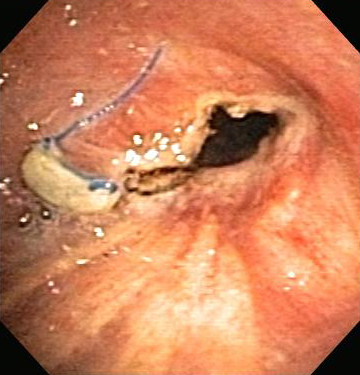

Contact or non-contact technique in which a high-frequency alternating electric current is delivered to the airway tissue for the relief of malignant and non-malignant CAO. [Figure caption and citation for the preceding image starts]: Post-lung transplant anastomotic bronchial stenosisFrom the collections of Jose Fernando Santacruz MD, FCCP, DAABIP and Erik Folch MD, MSc; used with permission [Citation ends].

[Figure caption and citation for the preceding image starts]: Post-lung transplant anastomotic bronchial stenosis: electrocautery radial incisionFrom the collections of Jose Fernando Santacruz MD, FCCP, DAABIP and Erik Folch MD, MSc; used with permission [Citation ends].